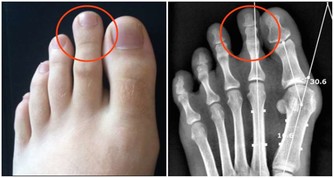

1、洗腳趾洗腳可謂是非常享受的一件事,每天晚上用熱水泡泡腳既解乏,又有利於睡眠,可以改善身體的血液循環,促進我們身體的新陳代謝,從而達到養生保健的目的。而且經常洗腳,對於預防和治療腳氣也是有一定的作用的。

很多人都覺得泡腳洗腳主要針對腳心就好了,其實腳指頭我們也是要經常搓一搓揉一揉的。

搓揉腳趾的作用:

我們在搓揉腳指頭的時候,腳趾尖有的會感覺到疼痛,而且也會覺得非常舒服,感覺到疼痛的時候,就說明我們的身體出現異常了。經常搓揉腳趾,可以促使我們的身體儘快恢復健康狀態,並且起到保健的作用。搓揉腳趾可以幫助食物的吸收和消化,消除我們身體的浮腫。